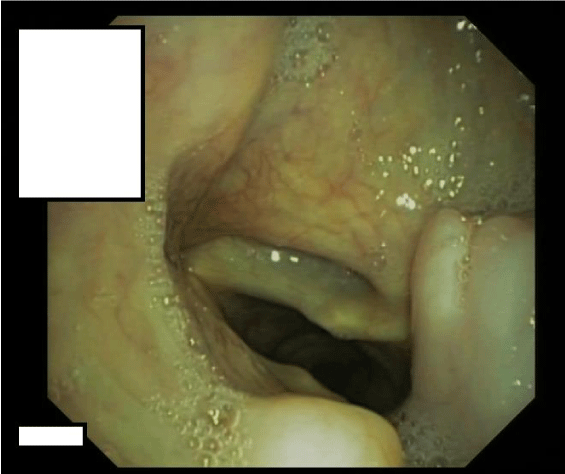

On flexible esophagogastroduodenoscopy, a large partially pedunculated submucosal soft tissue tumour, whitish-yellow in color, commencing at the proximal esophageal sphincter, and continuing down to the distal esophagus (Figure 1) was found. Flexible bronchoscopy revealed the proximal border of the tumour infiltrating both aryepiglottic folds (Figure 2) and a tracheal compression resulting in a tracheal stenosis of 30%. The right upper lobe bronchus appeared compressed with mucosal inflammation. However, the mucosa was not affected. Cytological examination of the bronchoalveolar lavage and repeated biopsies by flexible endoscopy failed to determine the diagnosis. Therefore, three consecutive rigid hypopharyngo-, microlaryngo- and esophagoscopies with multiple deep biopsies in different locations (hypopharynx, aryepiglottic folds and proximal esophagus) containing a total volume of more than 5 cc were performed. Pathological examination of these biopsies revealed a myxoid lesion, possibly a myxoid liposarcoma.

Figure 1: Esophagoscopic view: Submucosal soft tissue tumour of whitish-yellow color of the esophagus.